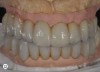

Fig 12 After all the teeth and some implants were extracted, a segmented, screw-retained, implant-supported reconstruction was fabricated and delivered.

Figure 12

Fig 14 Pretreatment and posttreatment views of the implant-supported reconstruction. Notice the favorable changes in the gingival outline and tooth proportions.

Figure 14